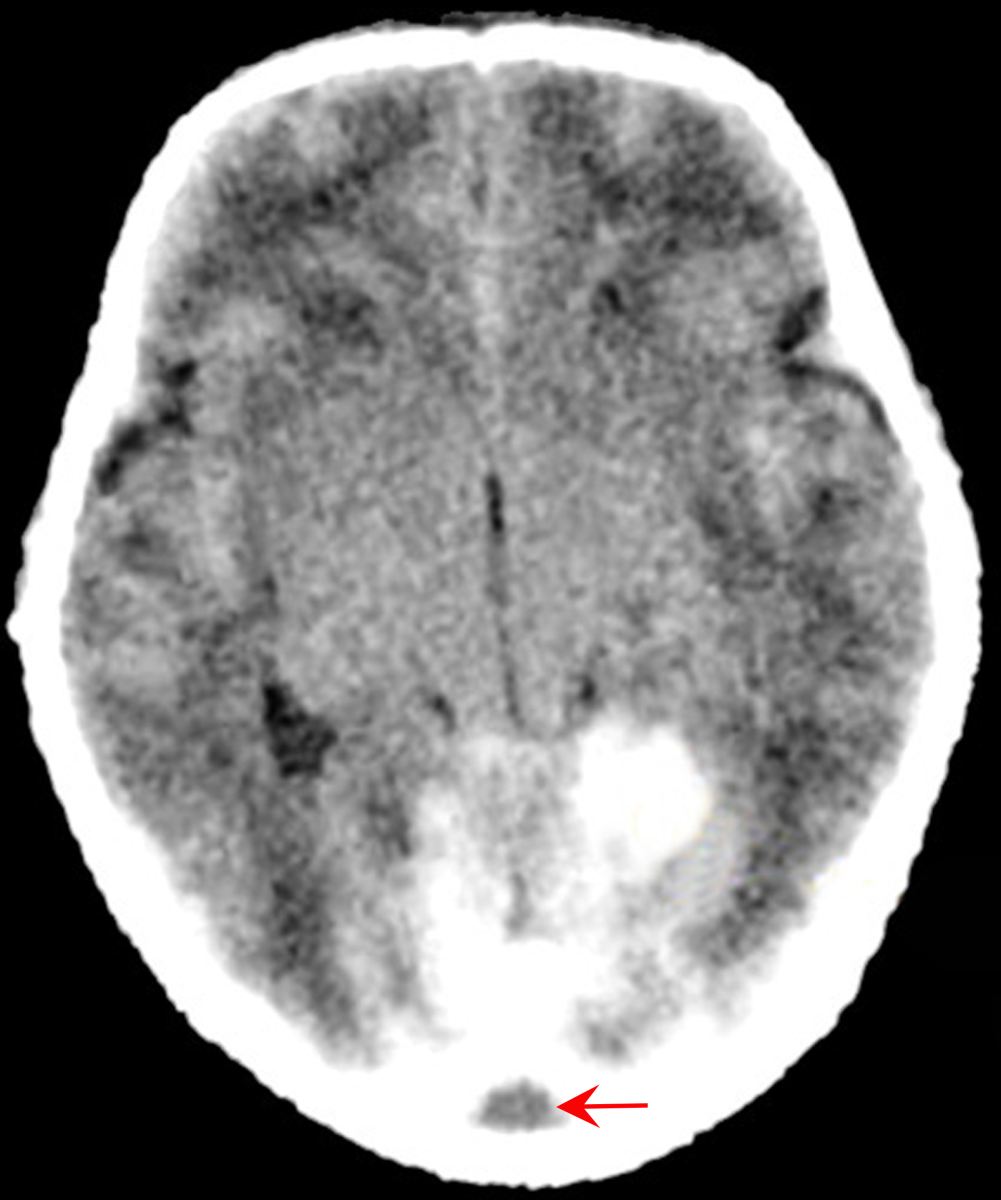

2、颅内出血 早产儿出血部位多在室管膜下和脑室内,足月儿多在大脑实质内(IPH)。其他如硬膜下出血(SDH)和蛛网膜下腔出血(SAH)在足月儿和早产儿都可发生。

缺氧缺血后脑部先出现水肿、软化、出血和坏死,以后形成空洞、脑室内、珠网膜下、硬膜下都可能出血、病程长者脑部可能萎缩。

1、大脑病变 足月儿的病变多在脑皮质,除水肿外尚有出血和坏死。形成小囊空腔后称多囊脑(spelencephaly),如形成大空洞称为空洞脑(porencephalen)。